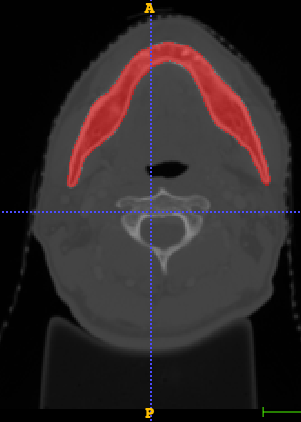

In Chapter 6, we propose an end-to-end, atlas-free 3D convolutional deep learning framework for fast and fully automated whole-volume HaN anatomy segmentation [115]. Our deep learning model, called AnatomyNet, segments OARs from head and neck CT images in an end-to-end fashion, receiving whole-volume HaN CT images as input and generating masks of all OARs of interest in one shot. AnatomyNet is built upon the popular 3D U-net architecture, but extends it in three important ways: 1) a new encoding scheme to allow auto-segmentation on whole-volume CT images instead of local patches or subsets of slices, 2) incorporating 3D squeeze-and-excitation residual blocks in encoding layers for better feature representation, and 3) a new loss function combining Dice scores and focal loss to facilitate the training of the neural model. These features are designed to address two main challenges in deep-learning-based HaN segmentation: a) segmenting small anatomies (i.e., optic chiasm and optic nerves) occupying only a few slices, and b) training with inconsistent data annotations with missing ground truth for some anatomical structures. We collect 261 HaN CT images to train AnatomyNet, and use MICCAI Head and Neck Auto Segmentation Challenge 2015 as a benchmark dataset to evaluate the performance of AnatomyNet. The objective is to segment nine anatomies: brain stem, chiasm, mandible, optic nerve left, optic nerve right, parotid gland left, parotid gland right, submandibular gland left, and submandibular gland right. Compared to previous state-of-the-art results from the MICCAI 2015 competition, AnatomyNet increases Dice similarity coefficient by 3.3% on average. AnatomyNet takes about 0.12 seconds to fully segment a head and neck CT image of dimension , significantly faster than previous methods. In addition, the model is able to process whole-volume CT images and delineate all OARs in one pass, requiring little pre- or post-processing. We demonstrate that our proposed model can improve segmentation accuracy and simplify the auto-segmentation pipeline. These contributions are released as an open-source software package called AnatomyNet, which is publicly available555https://github.com/wentaozhu/AnatomyNet-for-anatomical-segmentation. Portions of this chapter were published as part of [115].

- [121] W. Zhu and X. Xie. Adversarial deep structural networks for mammographic mass segmentation. arXiv:1612.05970, 2016.